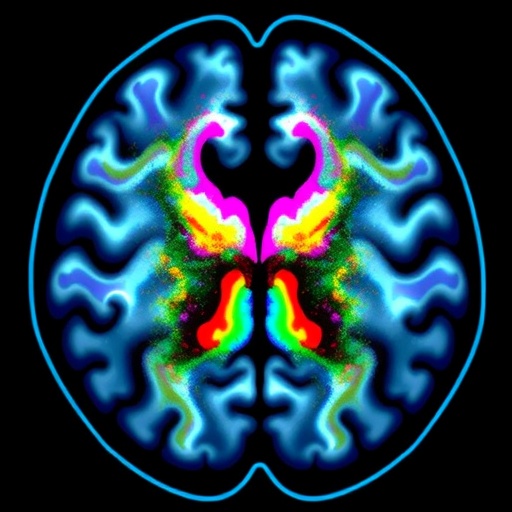

Glioblastoma (GBM), recognized as one of the most aggressive and fatal brain cancers, continues to present formidable challenges for effective treatment. Despite advancements in medical science, immunotherapy—a potent strategy that has revolutionized cancer treatment elsewhere—has yet to demonstrate significant efficacy in combating this malignancy. The overarching difficulty lies in GBM’s ability to evade immune detection, creating an immunologically “cold” tumor microenvironment that resists immune cell infiltration and activation. Emerging research from The University of Texas MD Anderson Cancer Center, published in Nature Communications, unveils a promising dual-targeting approach that may alter this grim landscape by enhancing immunotherapy responsiveness through simultaneous blockage of two critical immune evasion signals.

Cancer cells, including those in glioblastomas, have evolved sophisticated mechanisms to escape immune surveillance. Central to these defenses are what scientists term “don’t eat me” signals—molecular cues expressed on tumor cells that inhibit the engulfing and destruction capabilities of immune cells called macrophages. Macrophages are innate immune effectors known for their role as first responders; they patrol tissues to identify and phagocytose pathogens and abnormal cells. Under typical conditions, these cells also support adaptive immunity by processing tumor-derived antigens and presenting them to T cells, effectively educating these cytotoxic lymphocytes to recognize and eradicate malignant cells.

Intriguingly, the MD Anderson team has identified another critical immune checkpoint molecule, CD24, which operates similarly by functioning as a “don’t eat me” signal and is abundantly expressed on glioblastoma cells. CD24 interacts with the immune receptor Siglec-10 on macrophages, further impeding their capacity to engulf tumor cells. The redundancy of these immune evasion pathways suggests that targeting CD47 alone may be insufficient to unlock the full potential of the innate immune response against GBM. This discovery prompted an investigation into the combined blockade of both CD47 and CD24 to synergize and amplify immune-mediated tumor clearance.

The experimental approach implemented dual inhibition of these two signaling pathways alongside standard immunotherapeutic agents in preclinical glioblastoma models. Results demonstrated a significantly enhanced anti-tumor effect compared to monotherapies targeting either CD47 or CD24 alone. Macrophages, liberated from the inhibitory constraints imposed by both signals, exhibited substantially increased phagocytic activity, leading to elevated tumor cell clearance. Subsequently, this heightened activity facilitated the presentation of tumor antigens to T cells, catalyzing a robust adaptive immune response capable of eradicating malignancy more effectively.

This novel combination strategy addresses a fundamental issue in GBM treatment: the immune system’s failure to recognize and mount an effective assault on glioblastoma cells. By simultaneously disabling two independent “don’t eat me” signals, the immune system’s front-line defenders—macrophages—not only clear cancer cells more efficiently but also stimulate downstream T cell responses critical for sustained tumor suppression. This dual blockade approach effectively removes the “invisibility cloak” that tumor cells employ, thereby unmasking the cancer to the immune system.